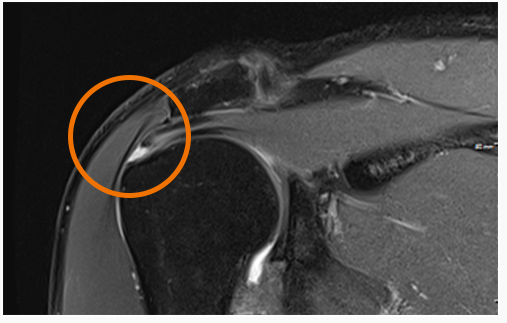

진단

초음파로 선별 검사 후 MRI로 정밀검사 필요 파열의 위치, 길이, 두께로 정확히 알아야 적절한 치료방법을 결정